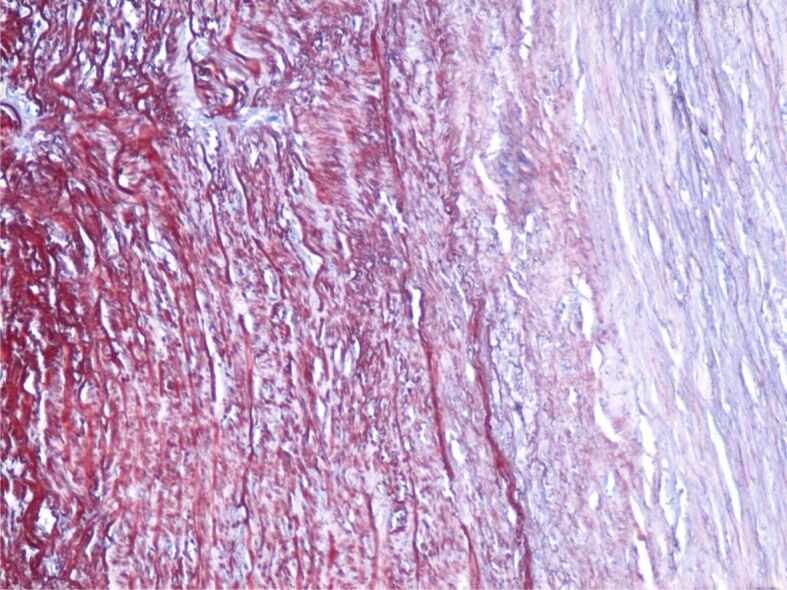

动脉瘤的定义是动脉壁扩张,直径超过相关血管正常直径的 1.5 倍。主动脉瘤(AA)可发生在任何部位,但大多位于腹部和肾下部,并延伸至髂动脉。主动脉瘤通常没有症状,最常见的情况是在对其他疾病进行各种成像检查时偶然发现。AA 的破裂通常很剧烈,是导致心脏性猝死的原因之一。手术治疗以及最近的血管内治疗是修复 AA 的唯一有效方法。在这项研究中,我们对有冠状动脉造影指征的稳定型劳累性心绞痛患者进行了 AA 诊断筛查。研究于 2021-2023 年期间在罗马尼亚蒂米什瓦拉心血管疾病研究所进行。在需要进行冠状动脉造影的 2458 名劳累性心绞痛患者中,有 1844 名患者(75%)至少有一个动脉粥样斑块狭窄,其中 312 名患者有 AA,其中 173 名患者位于腹主动脉水平。

An aneurysm is defined as a dilation of the arterial wall with a diameter exceeding 1.5 times the normal diameter of the vessel concerned. Aortic aneurysms (AAs) can develop at any level but are mostly found at the abdominal and infrarenal levels and extend to the iliac arteries. AAs are usually asymptomatic and are most often discovered incidentally during various imaging investigations for other conditions. Rupture of an AA is usually dramatic, being one of the causes of sudden cardiac death. Surgical treatment and, more recently, endovascular treatment are the only effective methods of AA repair. In this study, we screened for the diagnosis of AAs in patients with stable exertional angina who had indications for coronary angiography. The study was carried out in the period 2021-2023 in the Institute of Cardiovascular Diseases Timişoara, Romania. Of the 2458 patients with exertional angina who required coronary angiography, a number of 1844 (75%) patients had at least one stenotic atheromatous plaque, and of these 312 patients had AAs, of which 173 at the level of the abdominal aorta.